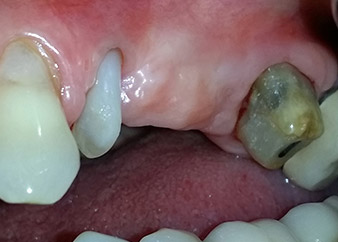

Eine 58-jährige Patientin, die auch eine gute Freundin und ärztliche Kollegin ist, beschwerte sich über Schmerzen und erhöhte Beweglichkeit ihres Brückenpfeilers 24. Es lag auch eine parodontale Entzündung vor, mit Taschentiefen von 7 mm mesiobukkal und mehr als 12 mm distal und einer Furkationsbeteiligung dritten Grades. Darüber hinaus zeigte die Röntgenaufnahme eine großflächige apikale Aufhellung am endodontisch (alio loco) vorbehandelten Zahn 24 (Abb. 1).

Einen Monat nach dem Eingriff waren sowohl die Schmerzen als auch die Entzündung an Zahn 24 minimal, die Zahnbeweglichkeit lag jedoch noch bei Miller-Klasse 2. Nach Freilegung und Reinigen des infizierten periapikalen und periradikulären Gewebes wurde das Ausmaß des Knochendefizits deutlich (Abb. 2 und 3).

An der bukkalen Wurzel fehlte der gesamte vestibuläre und distale Knochen. Das Attachment beschränkte sich weitgehend auf die palatinale Wurzel, was die anfängliche schlechte Prognose unterstreicht. Auch Zahn 27 wies ein verringertes horizontales Attachment (vgl. Abb. 12) und eine kleine apikale Aufhellung (Abb. 1) auf, allerdings ohne klinische Symptome.